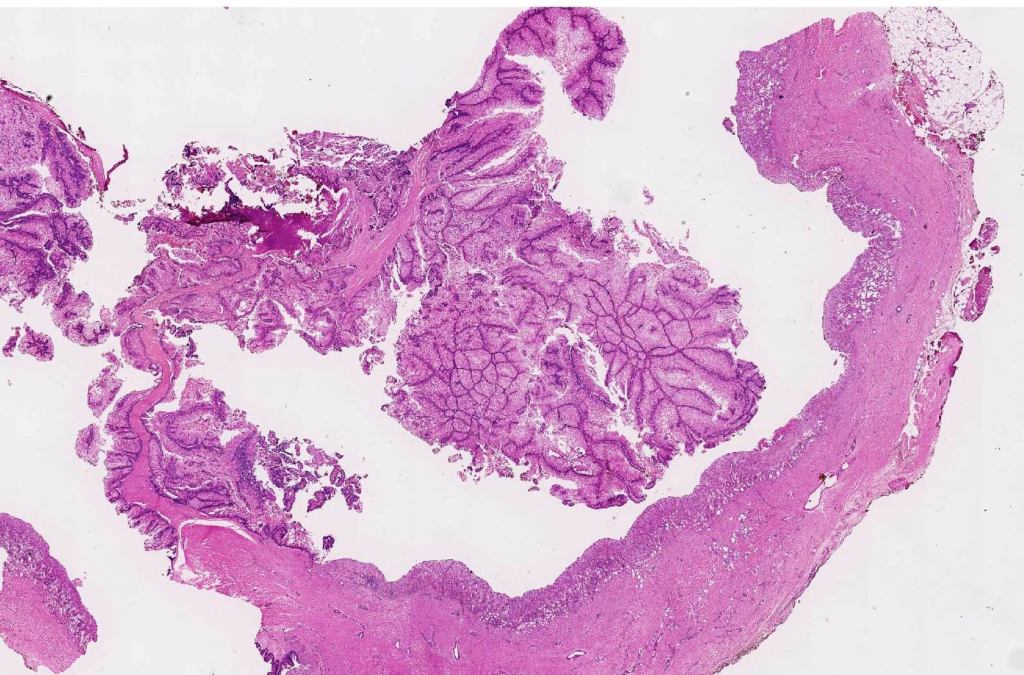

Histological features

•Variable origin from epidermis

•Typically multilobulated, occasioanlly cystic

•Collagenous pseudocapsule

•At the periphery, single or multiple germinative cell layers maturing into typical sebaceous cells (>50%)

•Variable peripheral palisading

•+/- basal mitoses (particularly in the so-called giant variant which should not be misdiagnosed as sebaceous carcinoma)